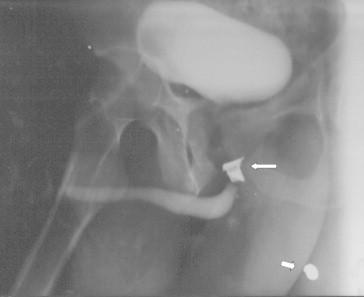

Of 45 patients, 29 (64%) were civilians and 16 (36%) were Iraqi military personnel. The injury was caused by an improvised explosive device (IED) in 25 (56%) patients and by individual firearms in 20 (44%). Of the patients, 24 had penile injuries, 15 had an injury to the bulbar urethra and six had an injury to the posterior urethra. Anterior urethral injuries were managed by primary repair, while posterior urethral injuries were managed by primary realignment in five patients and by a suprapubic cystostomy alone in one. An associated injury to major blood vessels was the cause of death in eight of nine patients who died soon after surgery (P < 0.001).

45例患者中,29例(64%)为平民,16例(36%)为伊拉克军事人员。损伤由简易爆炸装置(IED)导致的有25例(56%),由个人火器导致的有20例(44%)。患者中,24例有阴茎损伤,15例有球部尿道损伤,6例有后尿道损伤。前尿道损伤采用一期修复,后尿道损伤5例采用一期复位,1例仅行耻骨上膀胱造瘘术。9例术后不久死亡的患者中有8例因主要血管的合并损伤死亡(P<0.001)。